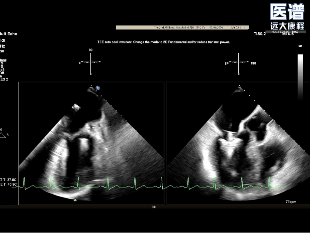

TEE-3D

病变位置为:A1邻近交界处脱垂;宽度/高度:1.08cm/0.29cm;A1/P1瓣叶长度:1.38cm/1.17cm;前后径(AP直径):3.56cm;二尖瓣口面积:4.39cm2

该例患者STS评分6.4%,为外科高风险。王建安院士、刘先宝教授及团队综合评估后,决定采取经导管TEER术作为治疗策略。考虑到术前经食道超声提示的A1区局灶性脱垂,术中拟于A1/P1交界区,应用团队自主研发的DragonFly经导管瓣膜修复系统,植入1枚长宽夹合器,以期实现对病变区域的有效夹合。